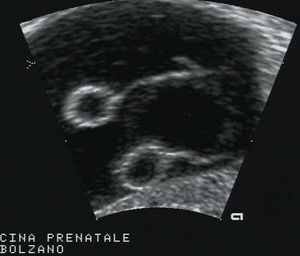

In a transvaginal coronal plane, you can see on the left-hand side of the fundus a flourishing pregnancy with an embryo of 9 weeks. In the last pictures of the clip a thin hypoechogenic endomiometrial layer is more easily seen.